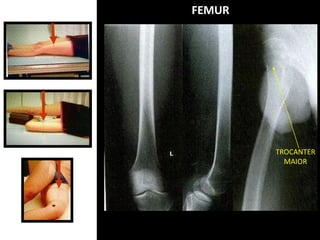

FEMUR

TROCANTER

MAIOR

ANATOMIA DO FÊMUR

Face

patelar

Cabeça do

fêmur

Trocânter menor

Trocânter

Colo

Côndilo lateral

Côndilo medial

Fossa (incisura)

Tubérculo

adutor

Superfície

poplítea